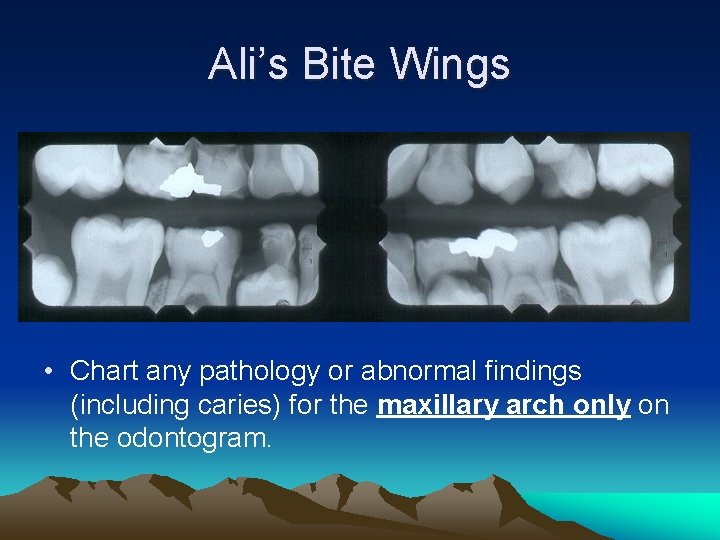

Ali’s Bite Wings

Ali’s Bite Wings • Chart any pathology or abnormal findings (including caries) for the maxillary arch only on the odontogram.